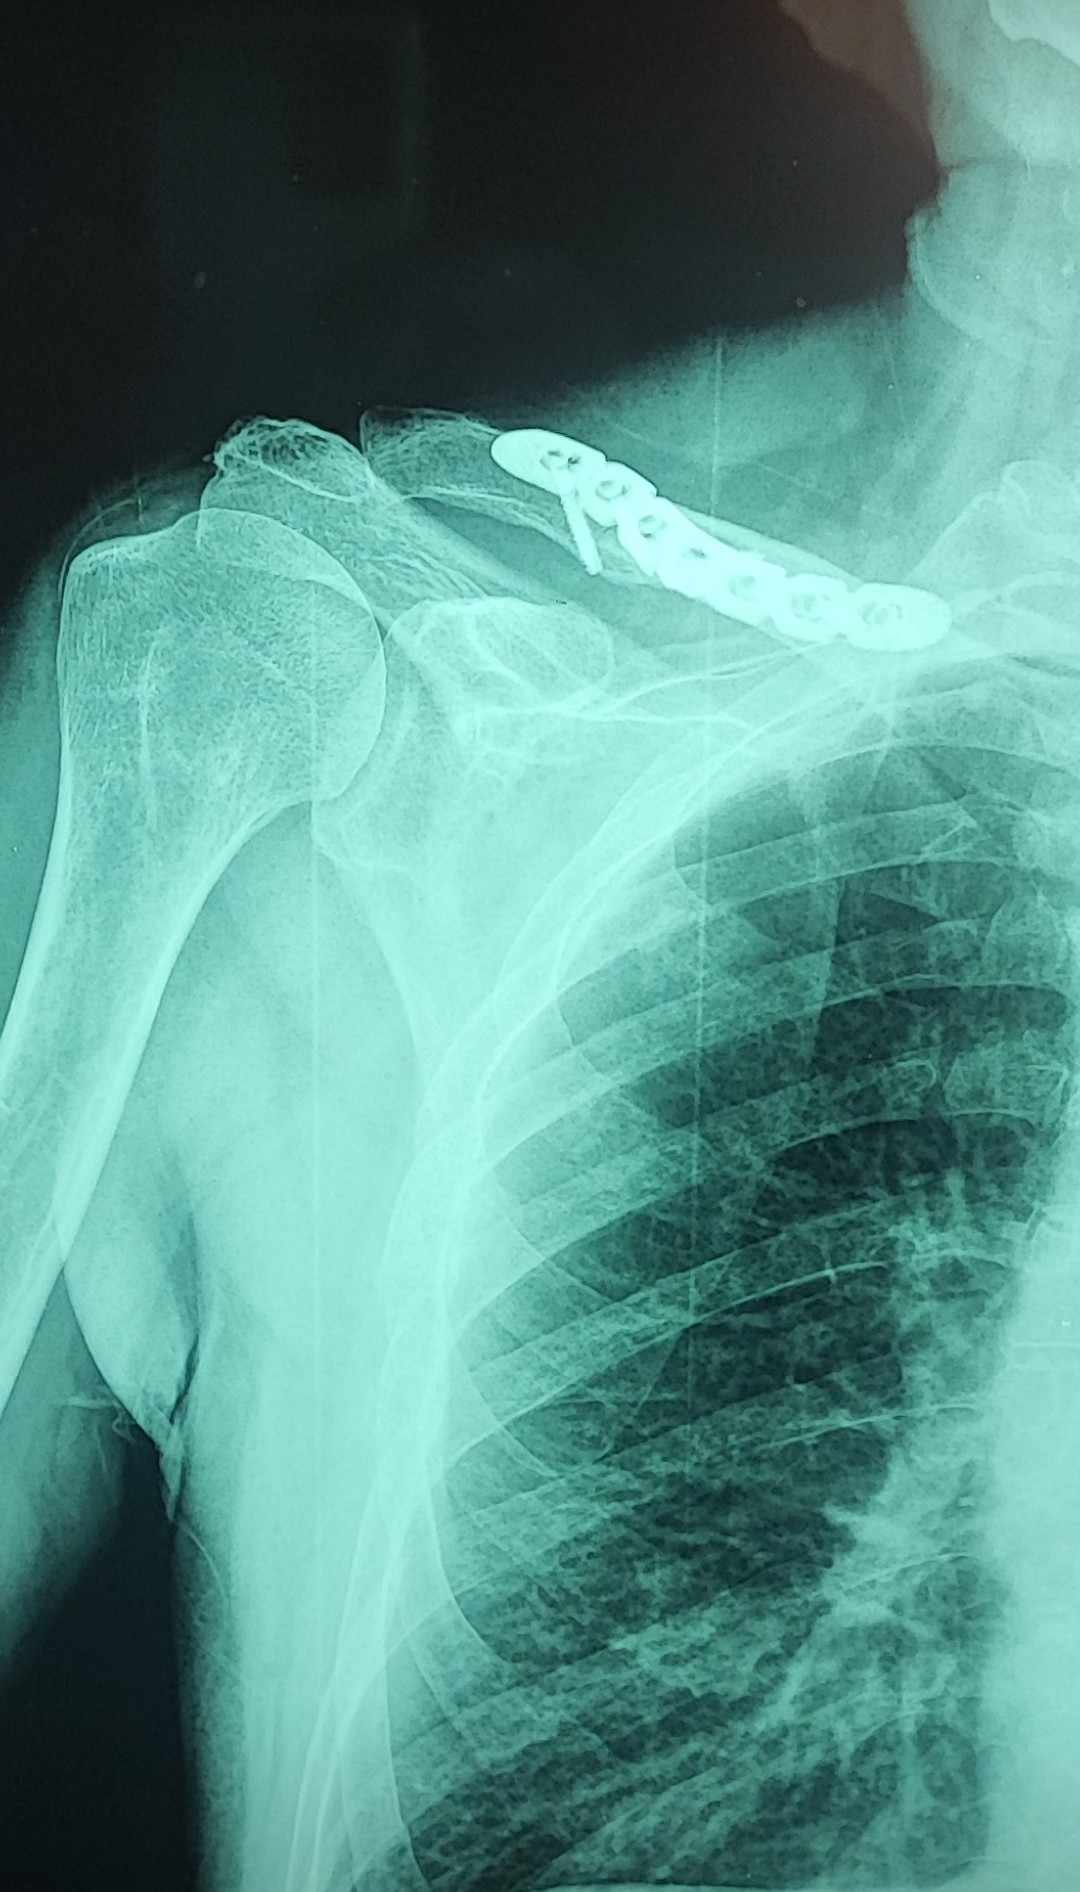

Evo desilo mi se sta se desilo,pao sa motora (citaj budala matora :) ) al to je ljubav...Jedva su me sastavili,kljucna (klavikula) na cetiri mesta,polomjena,rebra i neke sitnice...Cela poenta sta pisem je,sta bi bilo da bi ostao u privatnom sektoru,skoro 3 meseca nisam izasao od kuce,samo lekari,kontrole uhhh preko glave mi je sve

Bitno ide na bolje,e sad osecam na svaki pokret onu plocu titanijuma,ali sta je tu je...Sreca imao kacigu